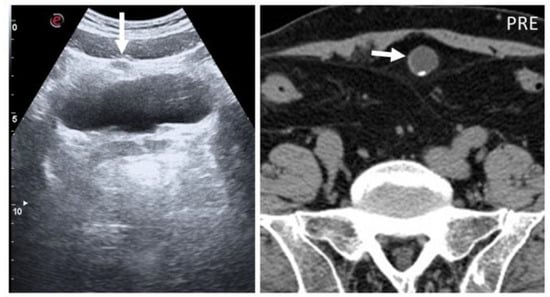

Figure 5. Urachal cysts are found along the superficial planes. On B-mode US, urachal anomalies appear as fluid-filled nodularity close to or in the context of the abdominal wall, incidentally found (arrow). As seen in axial, not-enhanced CT, small parietal calcification can also be seen (short arrow).